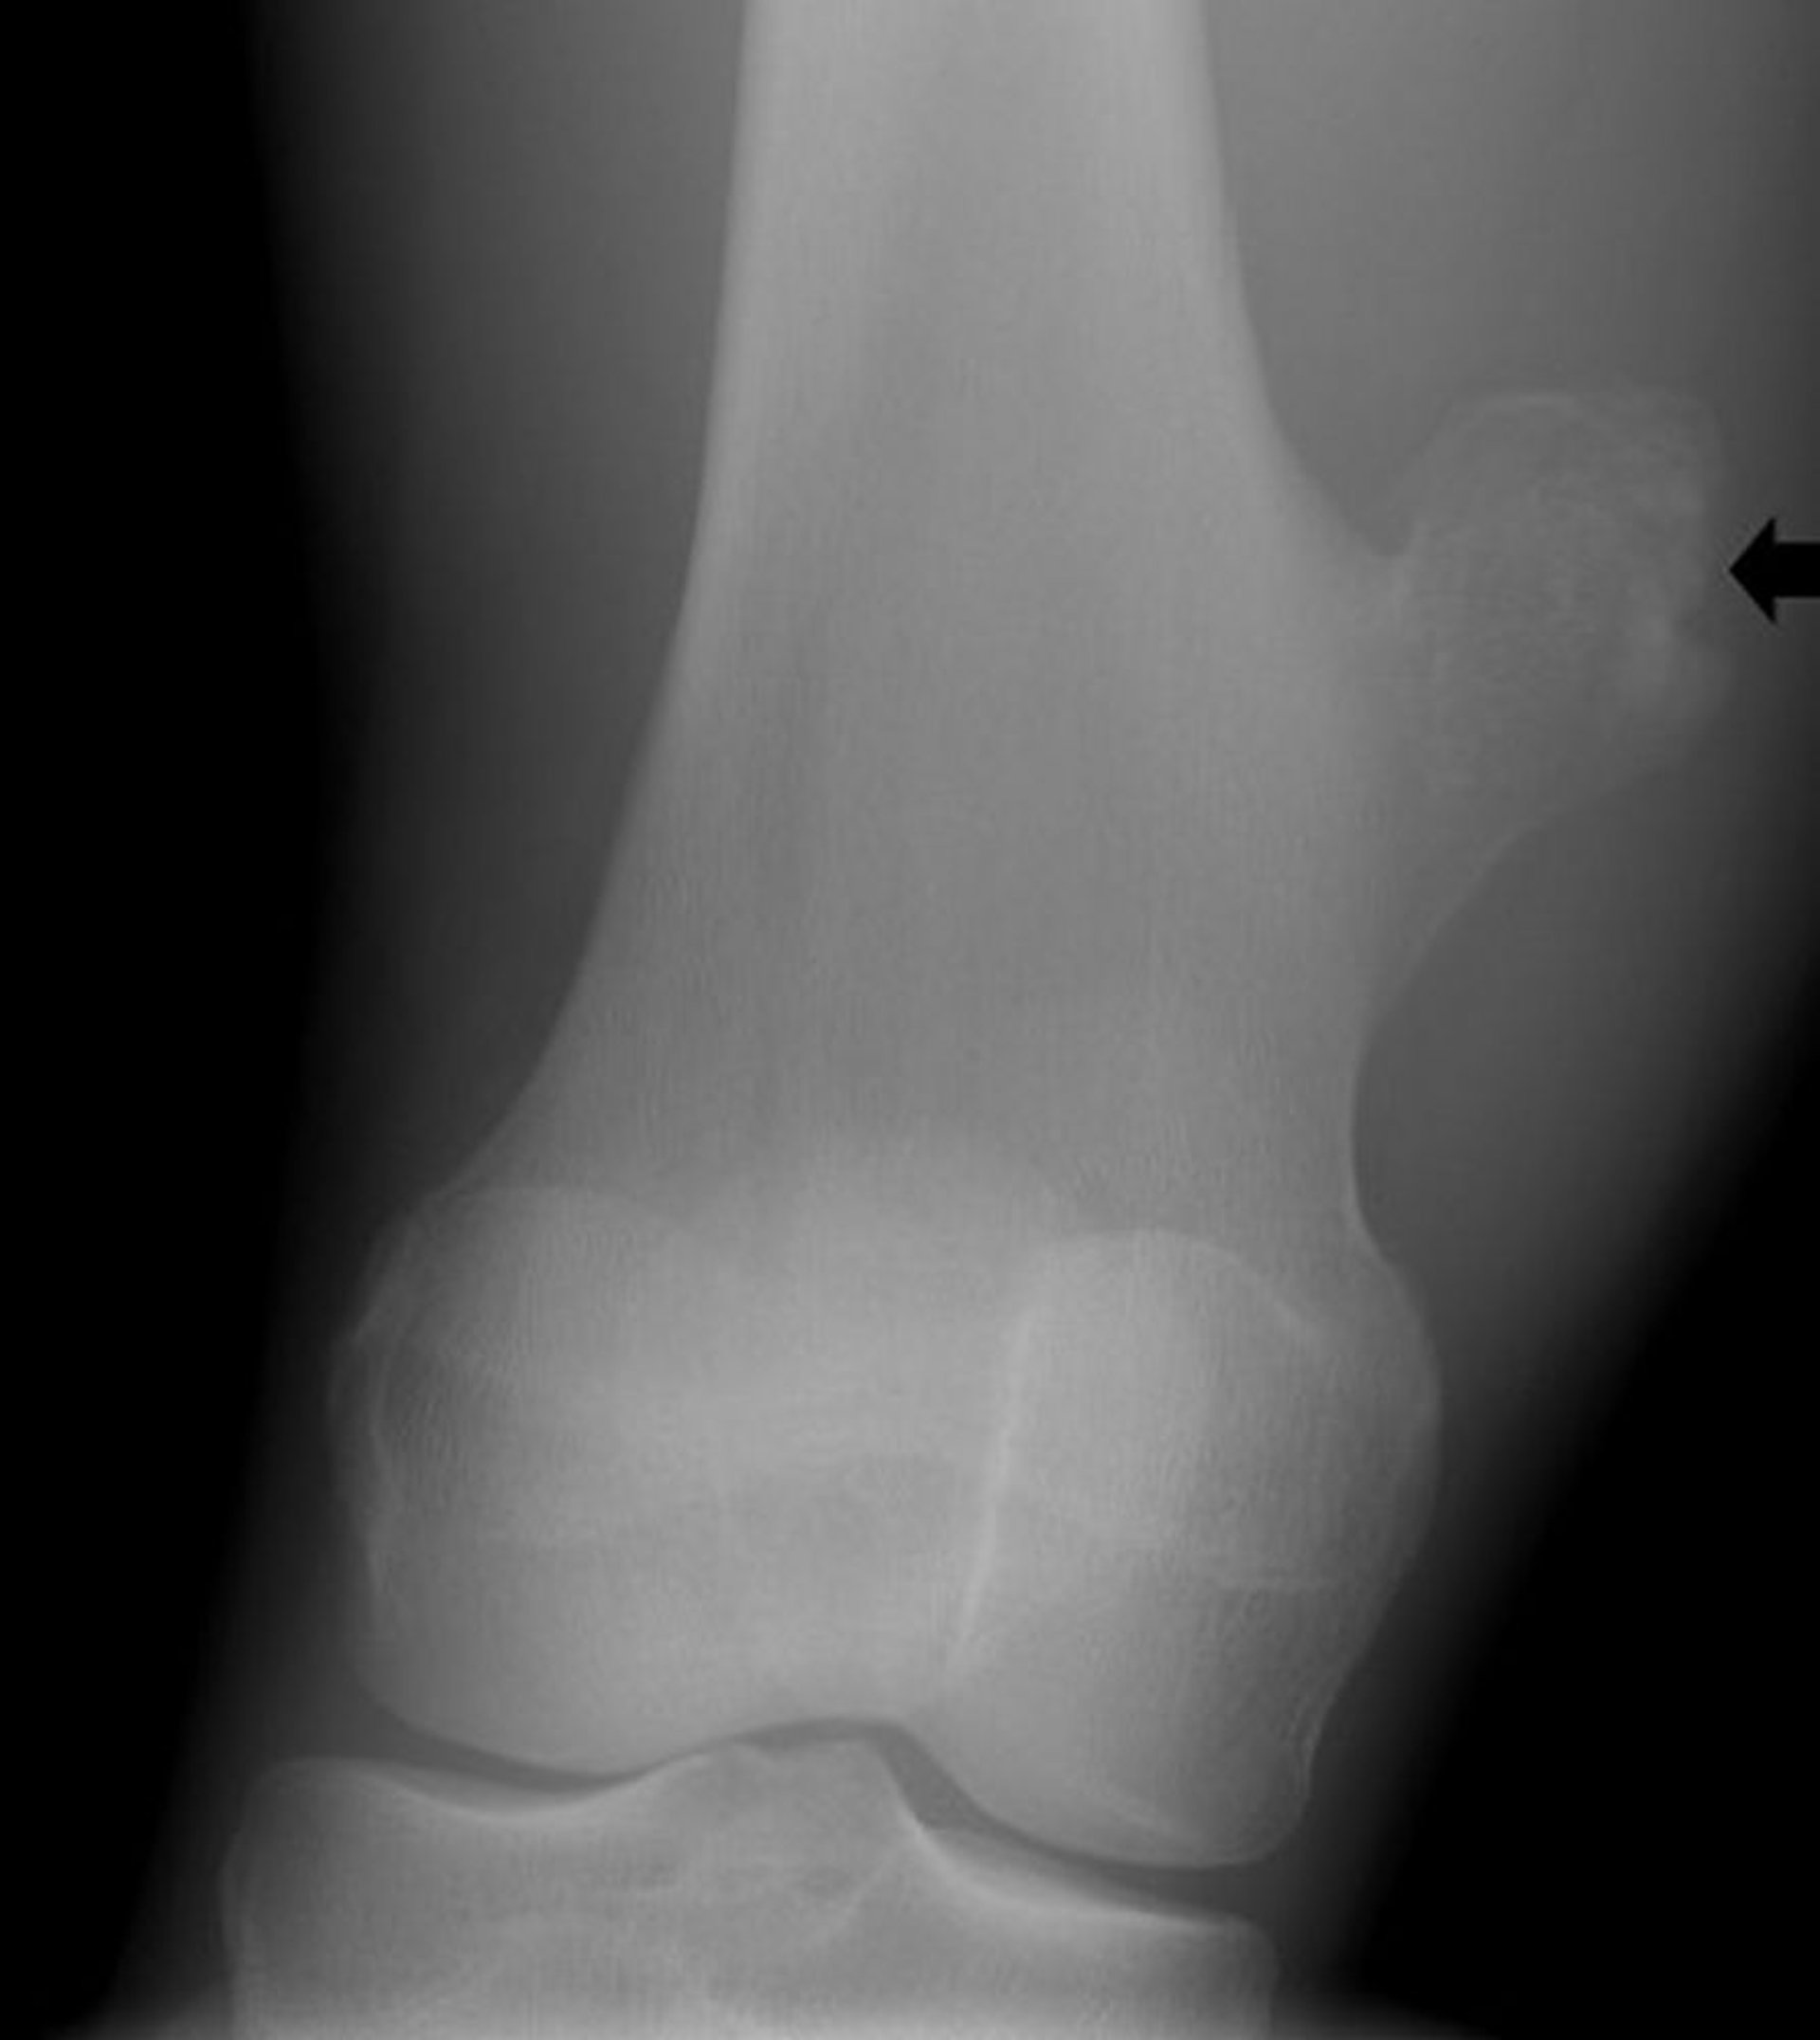

Osteocondroma de la rodilla

Esta radiografía de la rodilla muestra un crecimiento óseo (flecha) del fémur sobre la articulación de la rodilla, que es compatible con un osteocondroma.

Image courtesy of Michael J. Joyce, MD, and Hakan Ilaslan, MD.